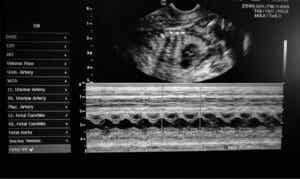

To niezwykle rzadki przypadek kliniczny, co sprawia, że bardzo trudno jest zebrać wystarczająco dużo informacji, które pomogłyby odkryć przyczynę jego występowania. Uważa się, że cyklopia jest wywoływana przez zaburzenia genetyczne lub spożywanie substancji toksycznych przez matkę w trakcie ciąży.

Weterynarz, który zajmował się psem cyklopem, stwierdził, że ciężarna samica zapewne spożyła toksyczne substancje przed porodem. Co więcej, była to starsza suczka, więc jej możliwości rozrodcze w naturalny sposób zmniejszyły się wraz z upływem czasu. Wszystkie te czynniki mogły doprowadzić w połączeniu do rozwoju takiej malformacji.